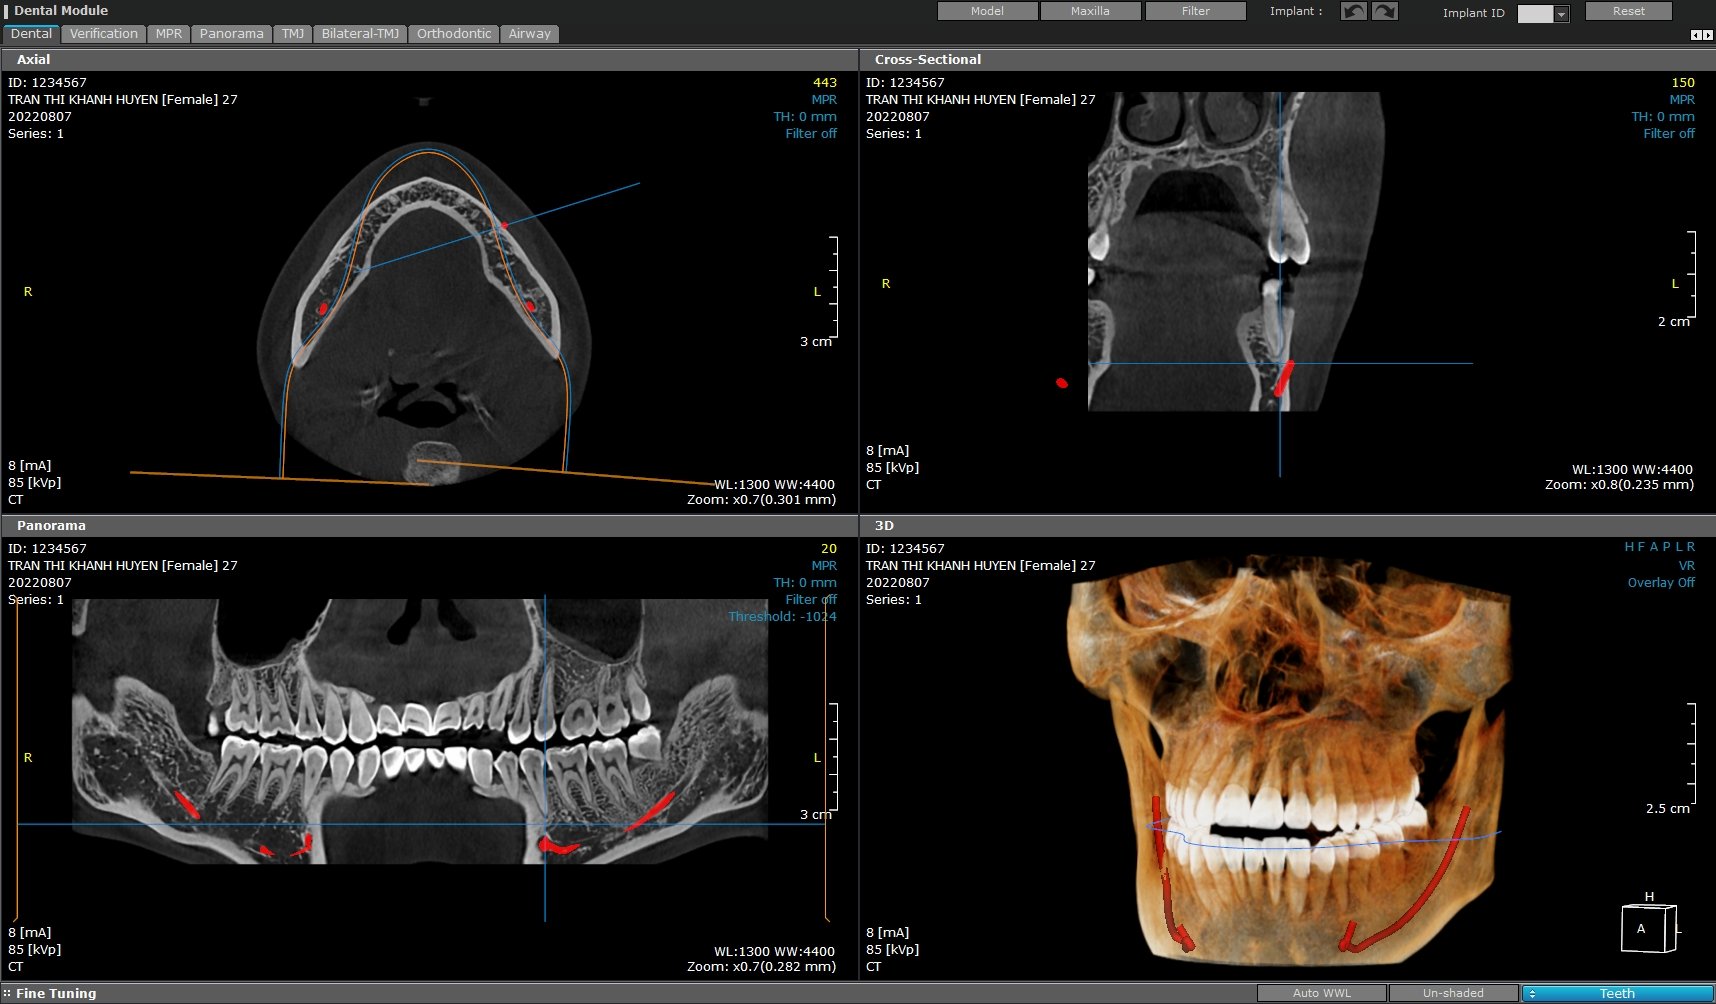

• Ứng dụng CBCT trong Implant nha khoa

Trong cấy ghép implant, CBCT đóng vai trò quan trọng trong việc đánh giá chính xác chất lượng và khối lượng xương hàm, vị trí của dây thần kinh và xoang hàm. Nhờ hình ảnh 3D chi tiết, bác sĩ có thể lên kế hoạch cấy ghép một cách tỉ mỉ, đảm bảo implant được đặt vào vị trí tối ưu, tăng khả năng thành công của ca điều trị.

CBCT cũng cho phép bác sĩ tạo ra các mô hình 3D của hàm răng, giúp trực quan hóa các cấu trúc giải phẫu và lên kế hoạch điều trị phức tạp như nâng xoang, ghép xương. Ngoài ra, CBCT còn được sử dụng để sản xuất máng phẫu thuật, giúp cho quá trình đặt implant trở nên chính xác và an toàn hơn.

• Ứng dụng CBCT trong chỉnh nha

Với CBCT, bác sĩ có thể phân tích chi tiết hình thái khuôn mặt, đo đạc các góc độ và tỷ lệ, giúp xác định các bất thường về xương hàm và răng. Thông tin này rất hữu ích trong các trường hợp cần kết hợp phẫu thuật chỉnh hình để đạt được kết quả điều trị tốt nhất.

Ngoài ra, CBCT còn giúp xác định chính xác vị trí của răng ngầm, răng khôn và các cấu trúc giải phẫu xung quanh. Nhờ đó, bác sĩ có thể lựa chọn phương pháp điều trị phù hợp, giảm thiểu rủi ro và tăng hiệu quả điều trị.